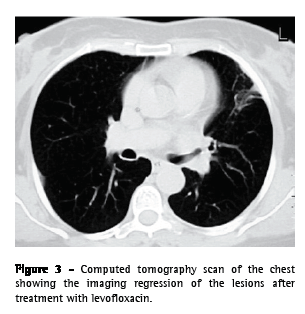

From the analytical study, we highlight the following results: an erythrocyte sedimentation rate of 98 mm in the first hour; a cancer antigen 125 level of 63.3 U.mL-1 (<35.0); a carcinoembryonic antigen level of 3.55 ng.mL-1 (<2.5); and a slight increase in the C-reactive protein level. The serum immunological study, the viral marker analysis, and the final analytical study revealed no other significant alterations. The results of colonoscopy, transabdominal pelvic ultrasound, mammography, and cervicovaginal cytology were normal. The first fiberoptic bronchoscopy performed showed diffused signs of inflammation at the level of the lingula. The cytological examinations of aspirate, bronchial lavage, and bronchoalveolar lavage were negative for neoplastic cells. Microbiological analysis under anaerobic conditions also yielded negative results, as did testing for acid-fast bacilli. The patient was then submitted to transthoracic needle aspiration biopsy (TNAB), which, in the extemporaneous cytological examination, showed an inflammatory process with suppuration. In view of this provisional result, antibiotic therapy with oral levofloxacin 500 mg daily was initiated, and it was decided that a second fiberoptic bronchoscopy should be carried out. However, the cytological examination of the TNAB revealed morphological aspects consistent with the presence of Actinomyces, confirmed through microbiological culture analysis of the bronchial and bronchoalveolar lavage of the second fiberoptic bronchoscopy, in which A. naeslundii was identified (Figure 2). Testing for acid-fast bacilli yielded negative results. Due to the clinical and radiological improvement after a month of treatment (Figure 3), we opted to maintain the antibiotic therapy already initiated, altering the dose schedule: intravenous levofloxacin (500 mg/day) for four weeks and oral levofloxacin (500 mg/day) thereafter. There were no adverse drug effects, and the treatment was continued for 16 weeks, until there was complete radiological normalization. Analytically, we observed a decrease in the erythrocyte sedimentation rate and in the initially altered levels of both tumor markers, as well as normalization of the C-reactive protein level. The patient was also submitted to dental treatment.